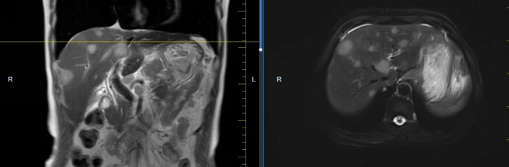

患者馬某某,男,60歲,因腹部不適行胃鏡及腹部CT,提示胃癌、多發(fā)淋巴結轉(zhuǎn)移、肝轉(zhuǎn)移,胃部病灶大小約11*6cm,淋巴結最大病灶約6*3cm,肝臟病灶最大約8.8*7cm。經(jīng)6周期化療+免疫,聯(lián)合中醫(yī)中藥后,病灶明顯縮小,進入維持治療階段,身體狀況與常人無異。

治療前